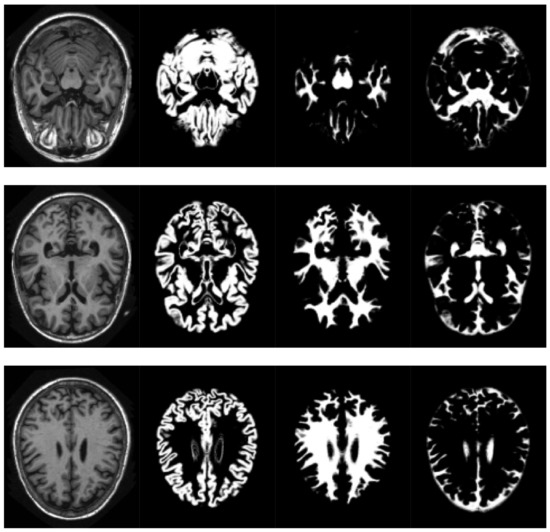

SPM models the brain as a layer of cerebrospinal fluid surrounding the gray and white matter. The prior probability that any voxel contains grey or white matter can be determined using a probabilistic atlas of tissue types. The main idea of this method is to model image intensities as a mixture of k Gaussians, where each Gaussian cluster is modelled by its mean, variance and a known tissue mixing proportion. In the unified model, multiple tissue probability maps are used as a priori information of the tissue classes. The Bayes rule is used to produce the posterior probability of each tissue class. This posterior probability is then combined with the data from the image to determine the final tissue type. Using this approach, two voxels with identical intensities can be identified as different tissues. An example of the results obtained can be seen in Figure 2.

Figure 2. Volume slices, selected from the pre-processed OASIS-1 dataset, showing tissue segmentation examples. Original T1-weighted MRI slice (left), gray matter probabilities (middle left),white matter probabilities (middle right), cerebrospinal fluid (right).